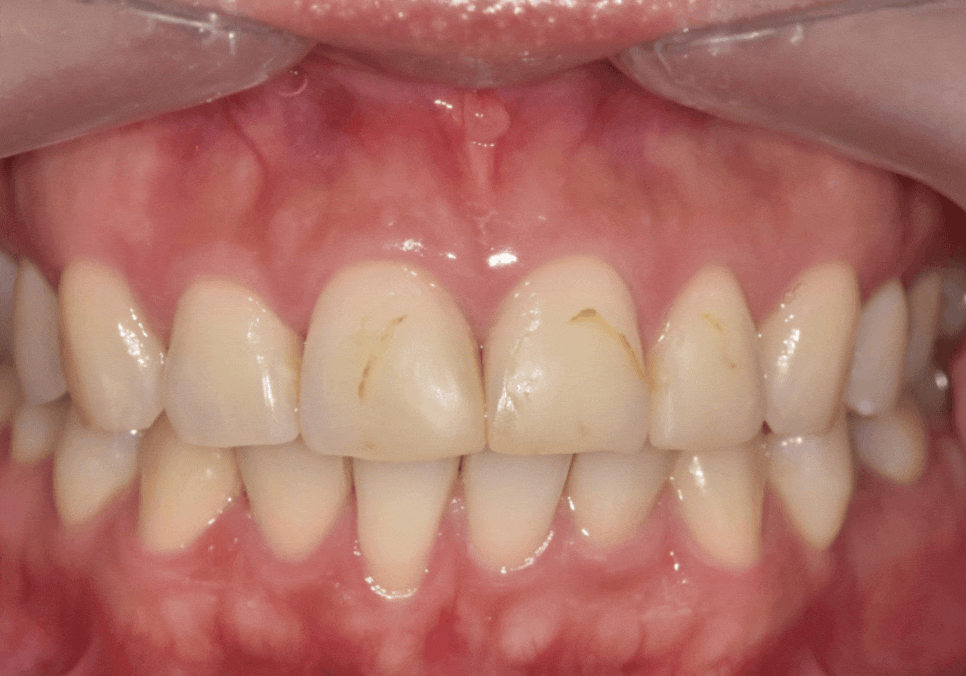

250726 (전/후)

레진 변색을 해결해드리고

약 5개월이 지나

환자분이 다시 내원하셨습니다.

251205

사진으로 보면

아주 크지 않아 보일 수 있습니다.